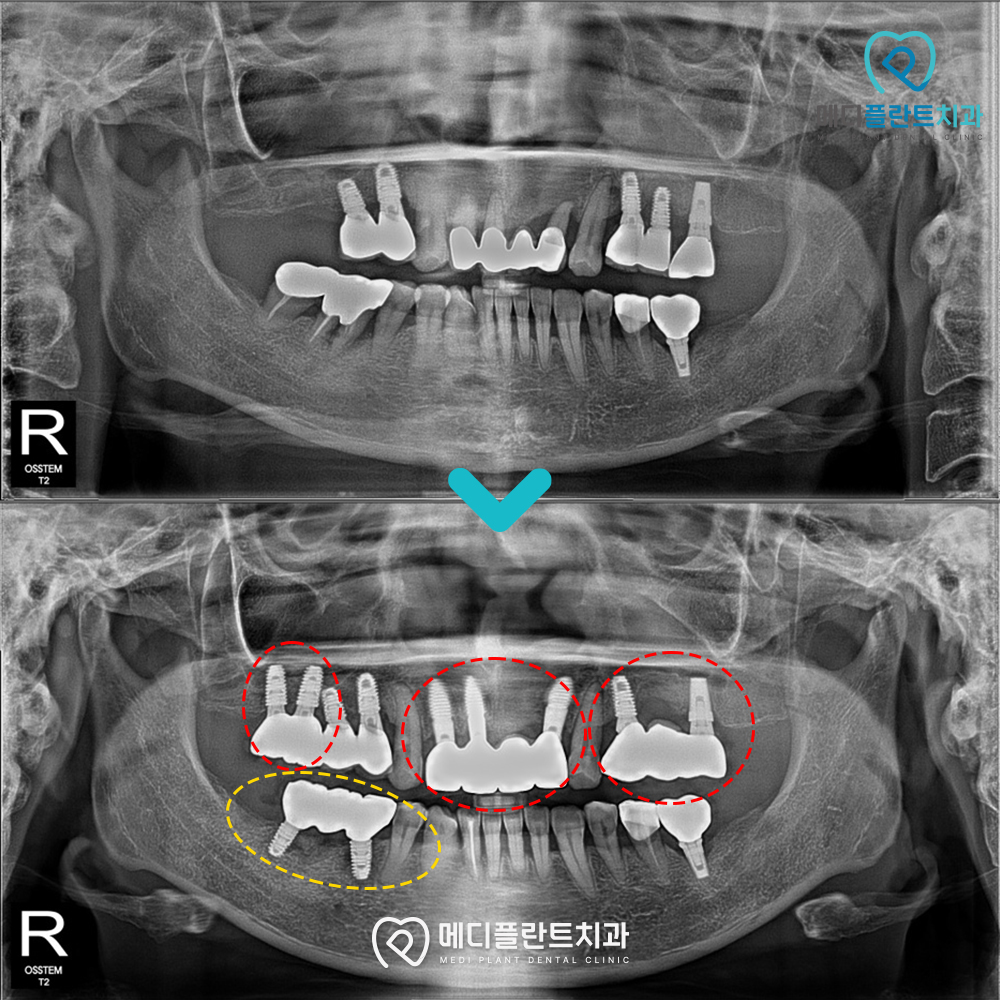

내원 당시 상악 좌·우측과

하악 좌측 일부 치아가 상실되어 있었고,

상악 일부 구간에는 기존 임플란트가 있었지만

전체 치아 배열의 균형이 맞지 않아

기능적·심미적 보완이 필요했습니다.

빨간색 점선 부분을 보시면

앞니는 기존 보철물이 이미 장착되어 있으나

재치료가 필요한 상태였습니다.

또한 어금니 일부 구간에도 기존 임플란트가 있었지만

보철물을 충분히 지지하지 못하는 상태였는데요.

이에 필요한 구간에 임플란트를 식립하고

노란색 점선 아래 하악 치아는

브릿지 형태의 임플란트를 연결하여

상실 부위를 보완하고 안정적인 저작 기능을 확보했습니다.